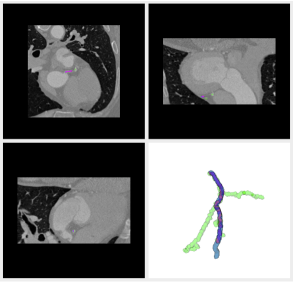

3.1.5 Carotids Data

Carotids are the vessels that irrigate the brain, and therefore are very important for many medical conditions such as the cerebrovascular accidents, commonly known as strokes. We also tested our algorithm in segmenting the carotid vessels, using the dataset carotid created for the 3rd MICCAI Workshop in the series ”3D Segmentation in the Clinic: a Grand Challenge III”.

The reference data available for this challenge concerns the identification of the carotid bifurcation. Even though the carotid vascular network reference is not available, it is possible to assess visually the outcome, since these vessels are morphologically simple, usually having a single main bifurcation. Figure 19 shows that both vessels and the bifurcation are found.